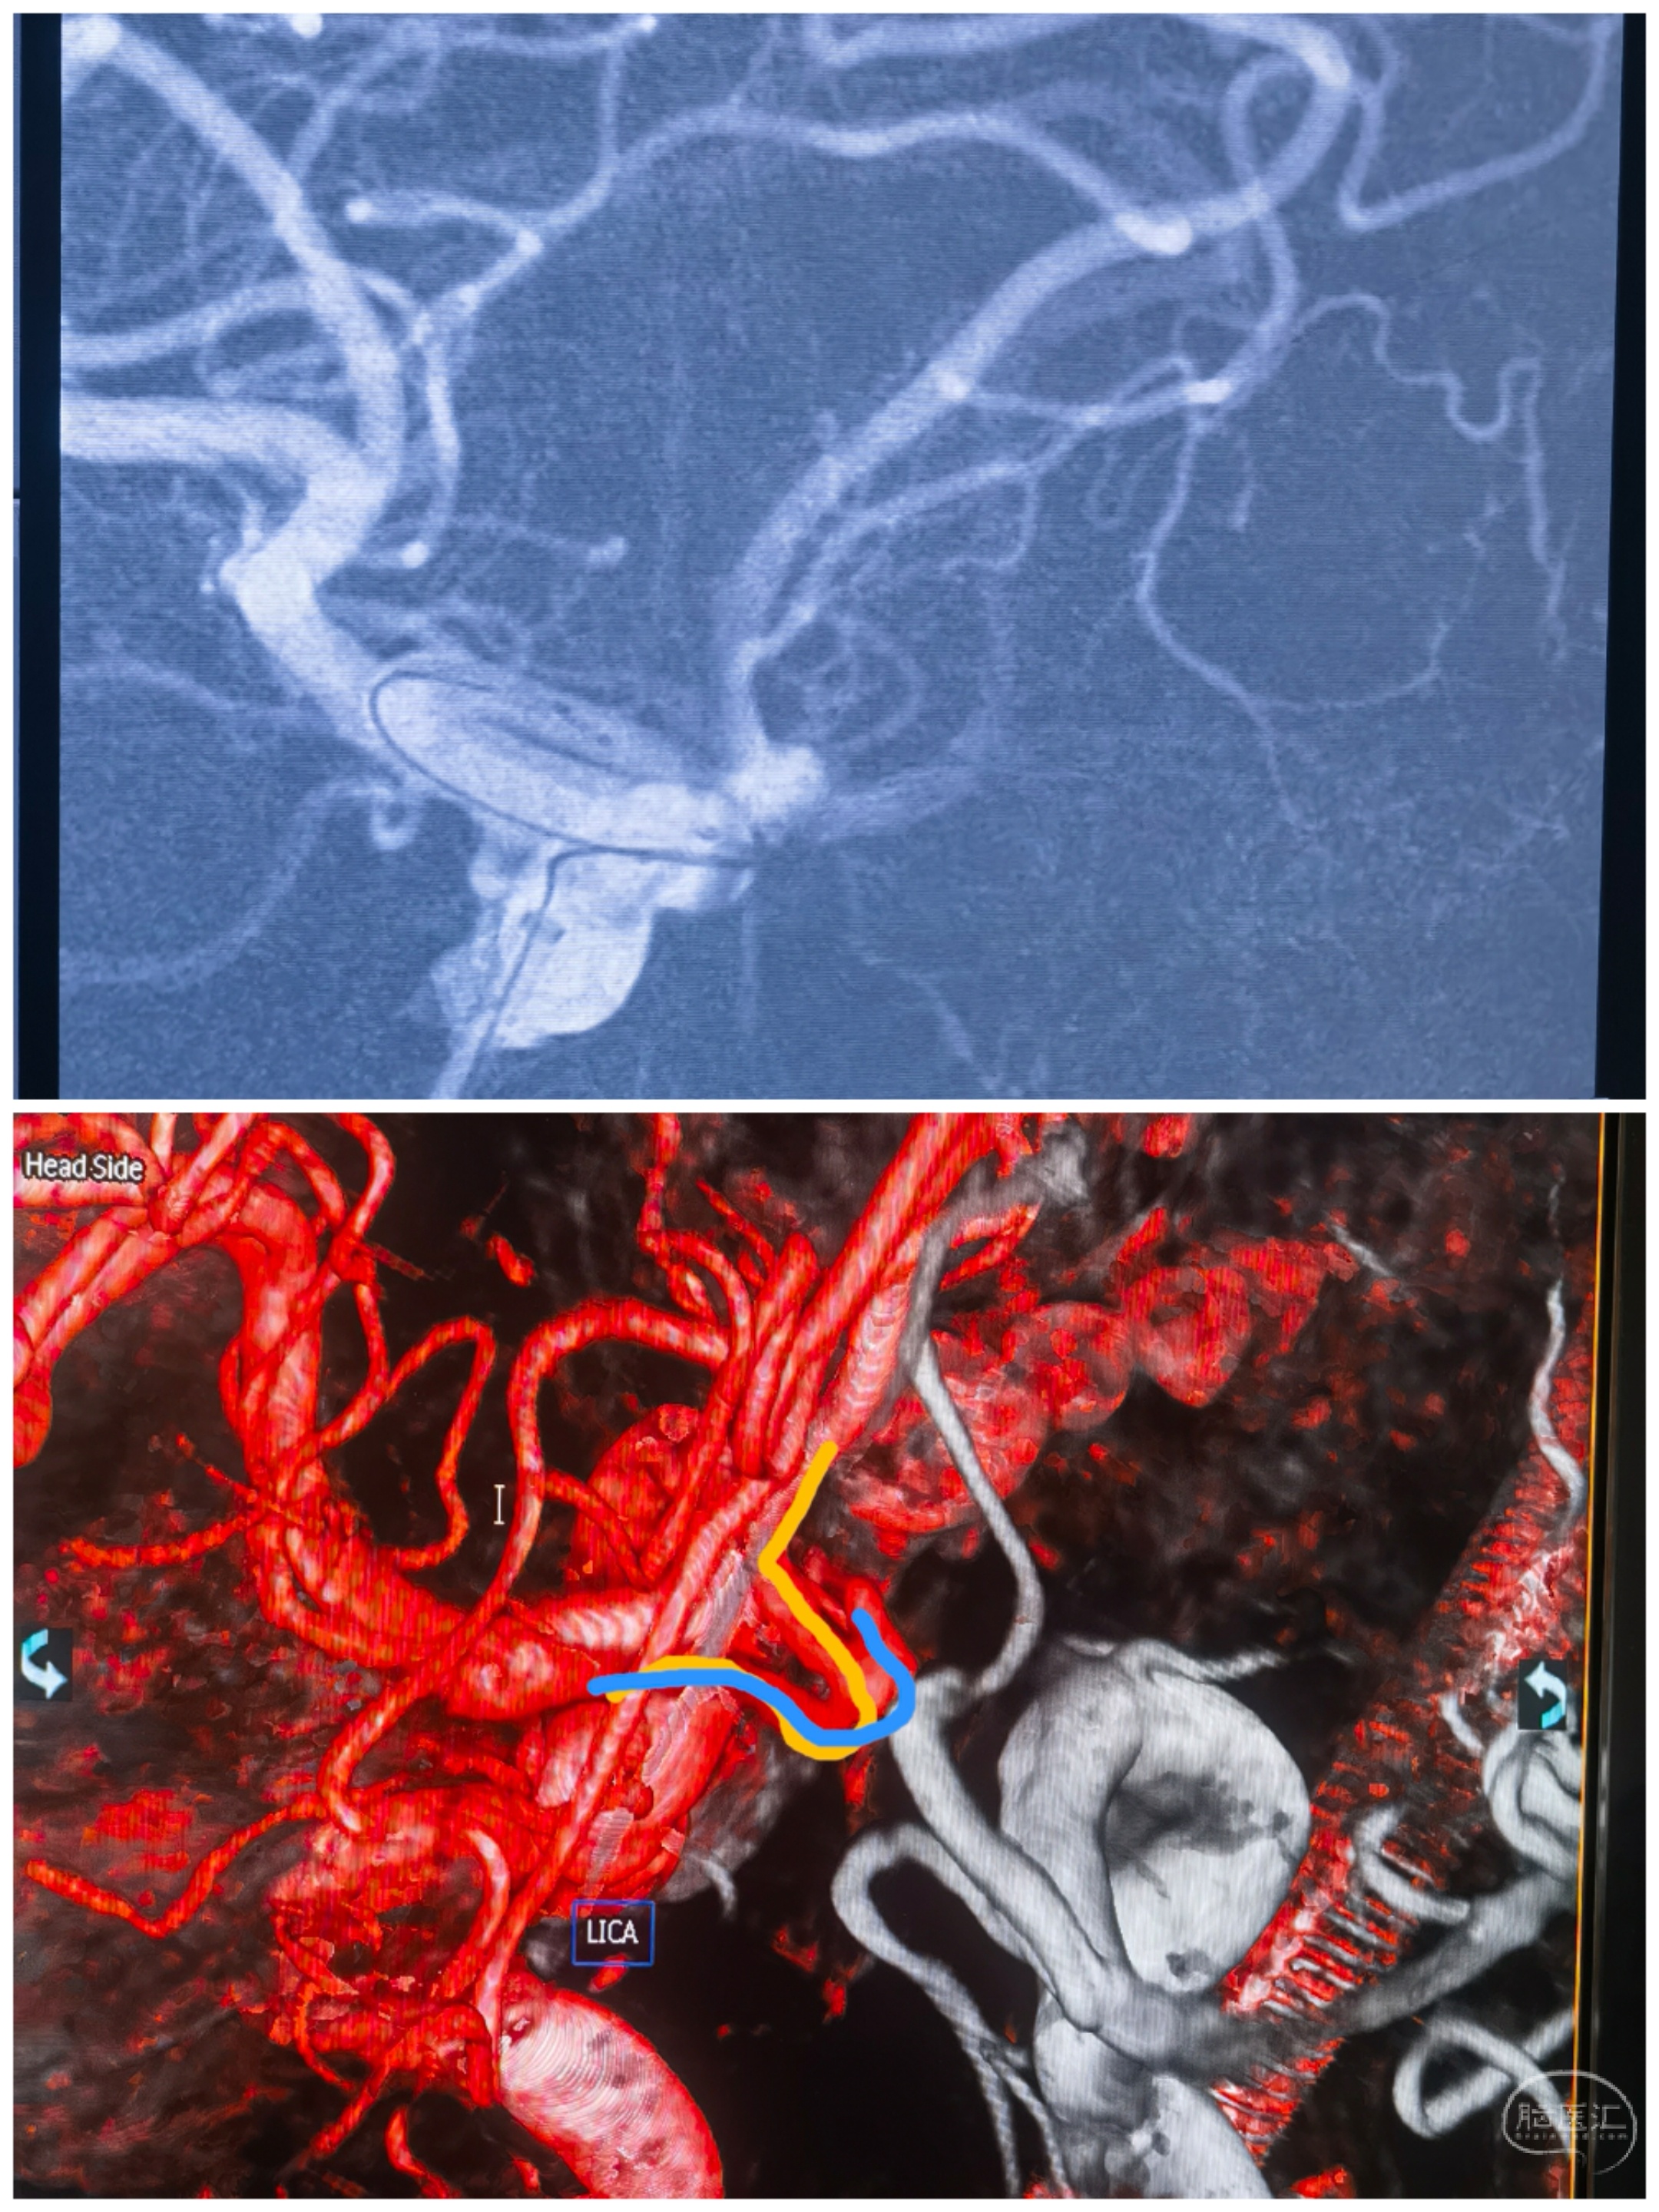

SAH入院,纵裂血肿

术前CTA,前交通动脉瘤,双侧A1独立

术前CTA情况

左侧颈内造影:左侧大脑前动脉优势供血,前交通动脉瘤显影

右侧颈内造影:非优势大脑前,前交通动脉瘤未见显影

3D重建

双侧颈内3D融合

结构分析

最初手术计划:左侧大脑前优势,左颈内造影前交通动脉瘤显影。拟经左侧通路治疗,左侧A1-左侧A2释放支架导管,左侧A1释放栓塞微导管。无奈左侧A1-左侧A2夹角锐利,支架导管无法通过😂😂

还好术前龙哥远程指导提醒了下,可以经右侧A1-前交通-左侧A2走支架导管。果断更换思路,经右侧通路,双侧同时路途。经右侧A1-前交通-左侧A2支架导管,右侧A1栓塞导管直接指向动脉瘤。

支架导管到位情况